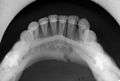

occlusal radiograph of a mandibular parasymphasis fracture